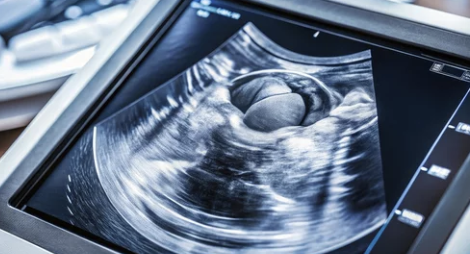

• 정기적인 검진: 조기 발견을 위해 정기적인 자궁경부암 검진과 초음파 검사가 권장돼요.

자궁암 검사는 자궁경부암 검사와 자궁내막암 검사가 있어요. 자궁경부암은 자궁 경부의 세포를 채취해 검사하는 방식이고, 자궁내막암은 초음파를 통해 자궁 내막 두께를 확인해 이상이 있는 경우 조직 검사를 시행해요. 정기 검진이 중요하므로, 최소 1년에 한 번씩 검진을 받는 것이 좋습니다.